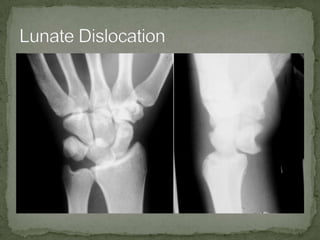

A 65-year-old female presented to the emergency department with right hand pain after falling down stairs. On examination, she had swelling of the right hand with limited motion of the wrist and hand. She was diagnosed with a lunate dislocation of the right wrist which requires emergent orthopedic consultation and may need to be repositioned in the emergency department or operating room. Complications are common after a lunate dislocation such as arthritis and wrist instability.